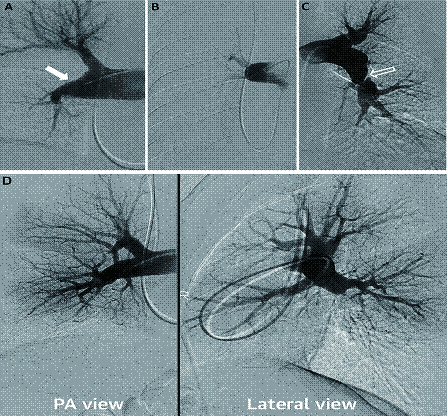

CTEPH肺动脉造影的特征性表现包括:带状或网状,内膜不规则,囊袋状缺损,血管突然狭窄,肺动脉完全阻塞等[39](图 3)。

根据血栓的位置,UCSD建议将CTEPH中的肺血栓栓塞分为各级:Ⅰ级:累及肺动脉主干;Ⅱ级:始于肺动脉段;Ⅲ级:始于肺动脉亚段;Ⅳ级:仅限于肺动脉亚段。此外,IC级为单只肺动脉完全闭塞,右肺动脉或左肺动脉完全闭塞,0级则未见相应肺内CTEPH(图 5)。值得注意的是,这种分类是在PEA术中进行的分类。随着成像方式的改进,术前预测疾病水平的能力有所提高,尽管不是所有情况都能进行预测。对于Ⅲ至Ⅳ级病变即使专业性更强的术者进行手术,并发症的发生率也更高,但手术成功后血流动力学仍有望得到改善。